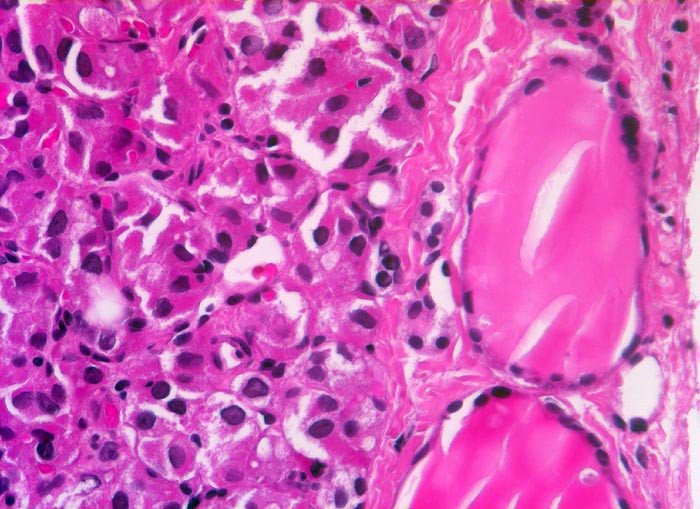

PathoPic – image database / PathoPic ID 5250 - follikuläres Schilddrüsenkarzinom

follikuläres Schilddrüsenkarzinom

Rechts im Bild zwei normale Follikel mit flachem Epithel und reichlich Kolloid. Die neoplastischen Follikel links im Bild sind sehr klein und enthalten kaum Kolloid. Die Tumorzellen haben vergrösserte polygonale Kerne und reichlich Zytoplasma.

Seit zirka 10 Jahren ist beim Patienten eine Struma bekannt. Jetzt sucht er den Hausarzt auf, weil er den Eindruck hat, die Schilddrüse sei grösser geworden. In der Ultraschall-Untersuchung wird ein Knoten im rechten Schilddrüsenlappen festgestellt, der relativ scharf vom angrenzenden Gewebe abgesetzt ist. Die Feinnadelpunktion ergibt eine follikuläre Neoplasie; eine Unterscheidung zwischen einem follikulären Adenom und einem follikulären Karzinom ist zytologisch jedoch nicht möglich. Es wird eine Hemithyreoidektomie durchgeführt und nach der Diagnosestellung eines follikulären Karzinoms eine Resthyreoidektomie angeschlossen.

Histologie

320